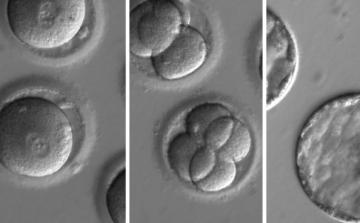

Úttörő módszerrel módosítottak emberi DNS-t

Először módosították úgynevezett \"bázis-szerkesztéssel\" humán embriók DNS-ét kínai tudósok, hogy kiiktassanak egy örökletes betegséget.

Először iktattak ki betegséget okozó DNS-t humán embrióból

Először metszettek ki sikerrel humán embrióból hibás DNS-darabot, amely egy öröklődő, súlyos szívbetegségért felelős - írta a BBC hírportálja a Nature tudományos folyóiratban szerdán megjelent tanulmány alapján.